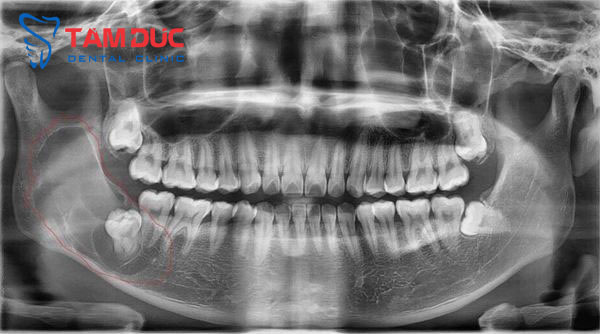

Bước 1: Khám tổng quát và chụp phim X-quang

Đây là bước xem xét, đánh giá vị trí, tình trạng… của răng khôn nhằm giúp bác sĩ lên phương án thực hiện phù hợp, an toàn cho khách hàng.